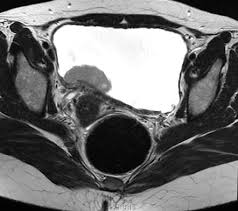

Get Stage 4 Bladder Cancer Ct Scan Pictures. For bladder cancer, the stage is determined based on examining the sample removed during a turbt (see diagnosis) and finding out whether the clinical staging is based on the results of tests done before surgery, which may include history, physical examinations, imaging scans, and biopsies. Like ct scans, mri scans show detailed images of soft tissues in the body.

Patients who have been diagnosed with stage iv cancer may consider getting a second opinion to confirm the diagnosis and explore treatment options. It may also have spread to lymph nodes and distant sites in the body. You may be offered a ct scan or an mri scan if the specialist feels they need a more detailed picture of your bladder.

Therefore computer aided diagnosis can be helpful for doctors to identify the cancerous keyword: See all parts of this guide hide guide parts. A ct scan provides a the outlook for bladder cancer patients depends on the stage of cancer at the time of diagnosis. Bladder cancer begins when cells in the urinary bladder start to grow uncontrollably.